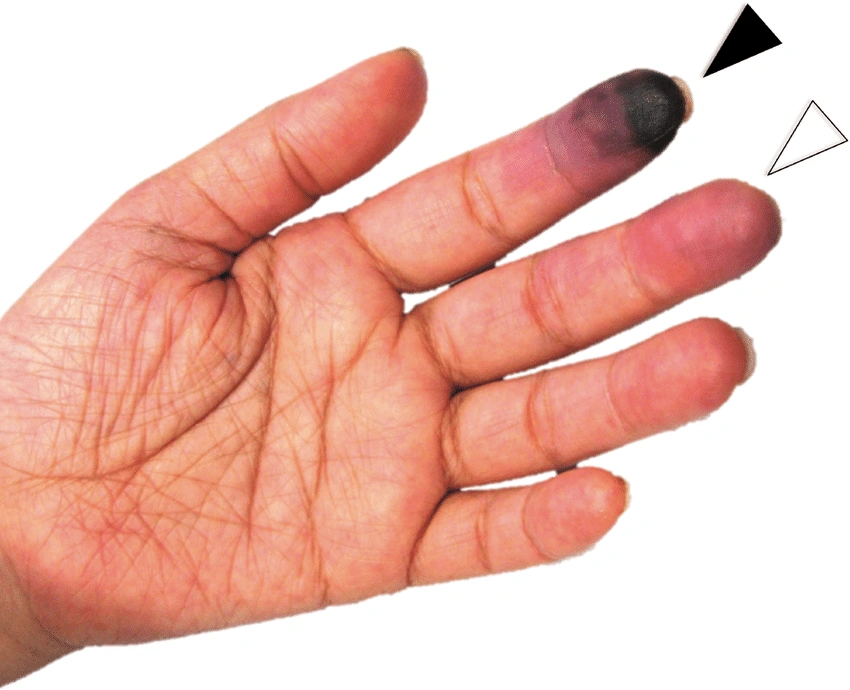

- تغير لون الجلد في منطقة محددة من الجسم، بحيث تصبح ذات لون أزرق شاحب، أو أرجواني، أو أسود، أو حتى أحمر، أو برونزي.

الغرغرينا الجافة

وهو ما يطلق عليها (Dry gangrene) وهو أكثر الأنواع شيوعًا، بالأخص بين مرضى السكر والأوعية الدموية وأمراض المناعة الذاتية، ينتشر هذا النوع في اليدين والقدمين ويكون سببه الرئيسي عدم وصول الدم لهذه الأجزاء أو ضعفه فيها؛ مما يُميت الأنسجة ويغير لونها، وجدير بالذكر أنه يمكن تطور هذا النوع إلى الغرغرينا الرطبة بأنوعها المختلفة.